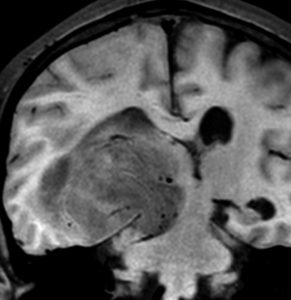

典型的な膠芽腫のガドリニウム増強画像です。右の側頭葉から発生したために目立った症状が無く,この大きさで発症しました。何となくボッとしていると言うのが訴えでした。腫瘍の周囲がガドリニウムで白く増強されて,内部は壊死で低信号(黒っぽい)になっています。

左がガドリニウム増強像で,手術ではこの部分が取れれば全摘出といわれるのですが,実際は右側のフレア画像で白っぽく見える所には腫瘍が滲み込んでいます。この部分を全て摘出してはじめて,画像上の全摘出といいます。全摘出は無理でしょう